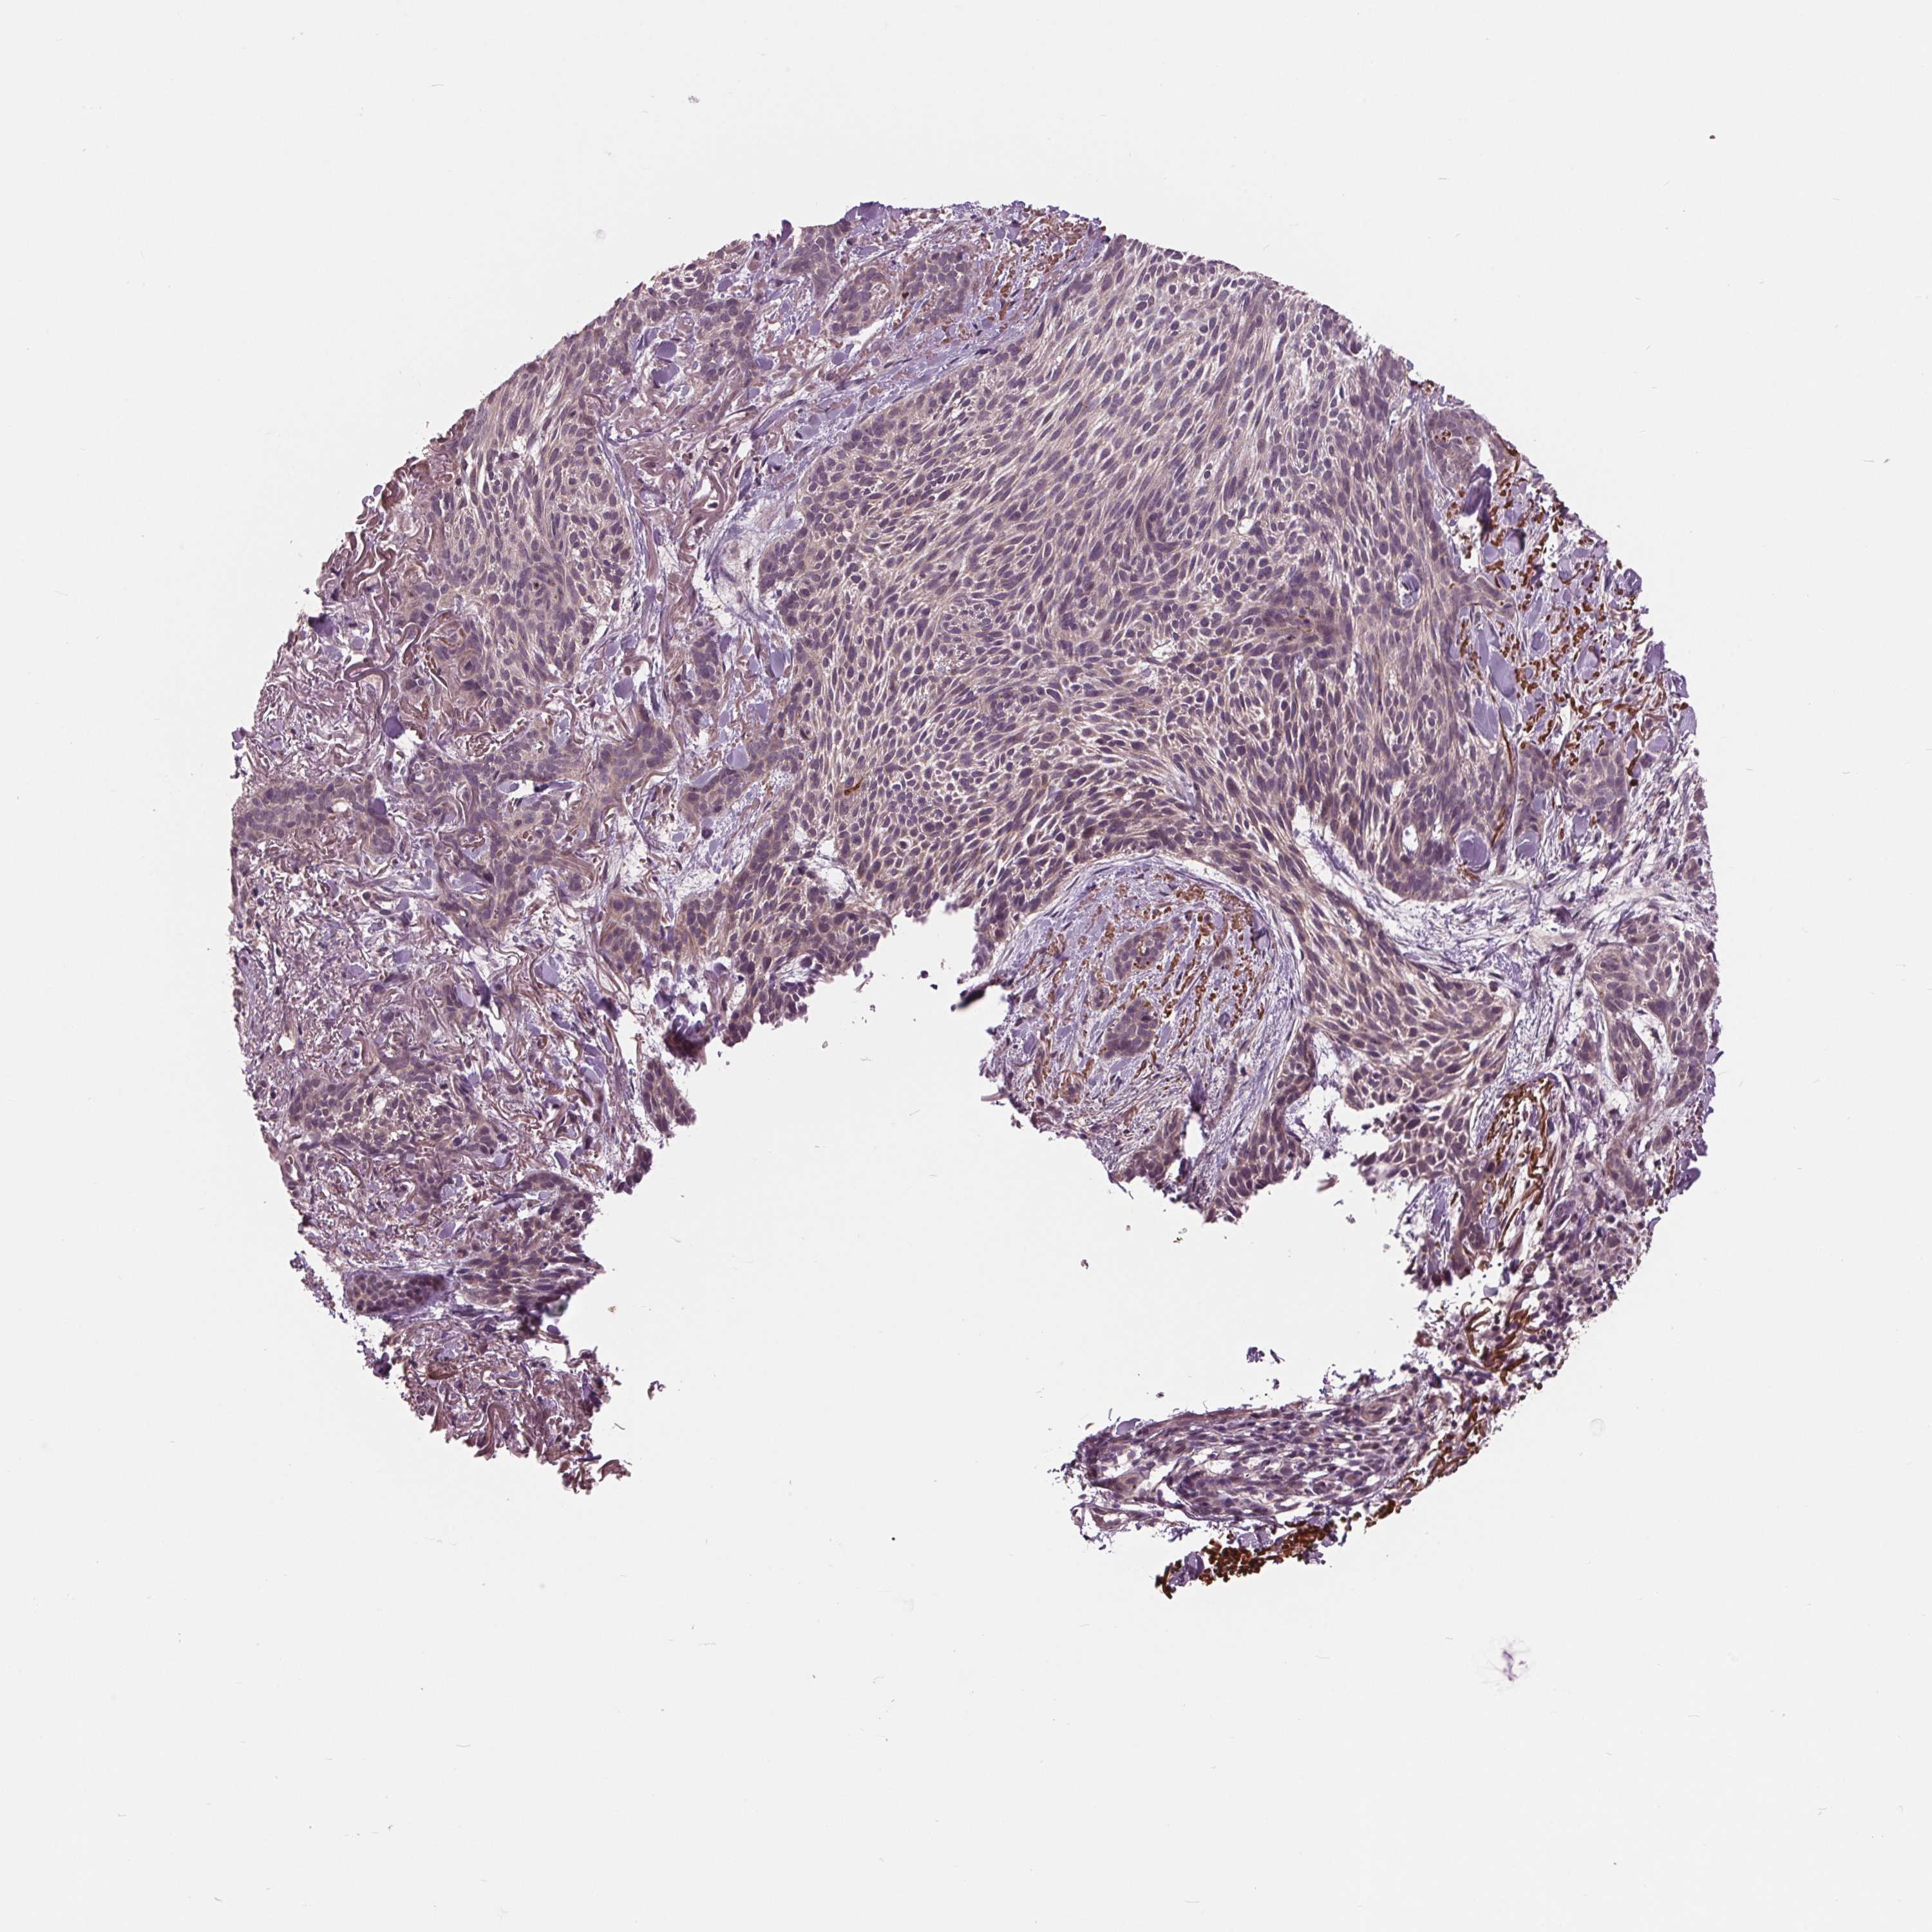

Basal cell and squamous cell cancer

SKIN CANCER - Protein expressioni

A mouse-over function shows sample information and annotation data. Click on an image to view it in a full screen mode. Samples can be filtered based on level of antibody staining by selecting one or several of the following categories: high, medium, low and not detected. The assay and annotation is described here.

Antibody stainingi

Antibody staining in the annotated cell types in the current human tissue is reported as not detected, low, medium, or high, based on conventional immunohistochemistry profiling in selected tissues. This score is based on the combination of the staining intensity and fraction of stained cells.

Each image is clickable and will lead to virtual microscopy that enables deeper exploration of all samples and also displays staining intensity scores, fraction scores and subcellular localization as well as patient and tissue information for each sample.

Antibody CAB004463

Antibody CAB069396

Staining

High

Medium

Low

Not detected

Intensity

Strong

Moderate

Weak

Negative

Quantity

>75%

75%-25%

<25%

None

Location

Nuclear

Cytoplasmic/membranous

Cytoplasmic/membranous,nuclear

Basal cell carcinoma